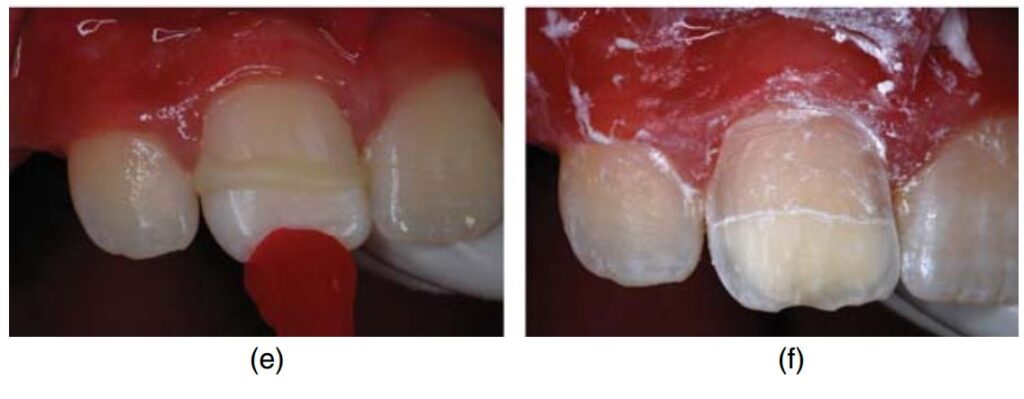

Hình 17.5. Lấy tủy buồng với canxi hydroxit và phục hồi thân răng cửa giữa hàm trên sau chấn thương. (a) Răng chấn thương nhìn từ mặt ngoài. (b) Nhìn từ rìa cắn thấy lộ tủy.

(c) Hình ảnh sau khi lấy tủy buồng và cầm máu. (d) Đặt canxi hydroxit.

(e) Gắn lại phần thân răng gãy bằng cement glass ionomer phối hợp nhựa (RMGI). (f) Mài sửa soạn để chuẩn bị thực hiện veneer composite lên mặt ngoài.

(g) Bôi bond (tự etching). (h) Hình ảnh răng sau 26 tháng.

(i) Hình ảnh X quang 26 tháng sau khi điều trị.